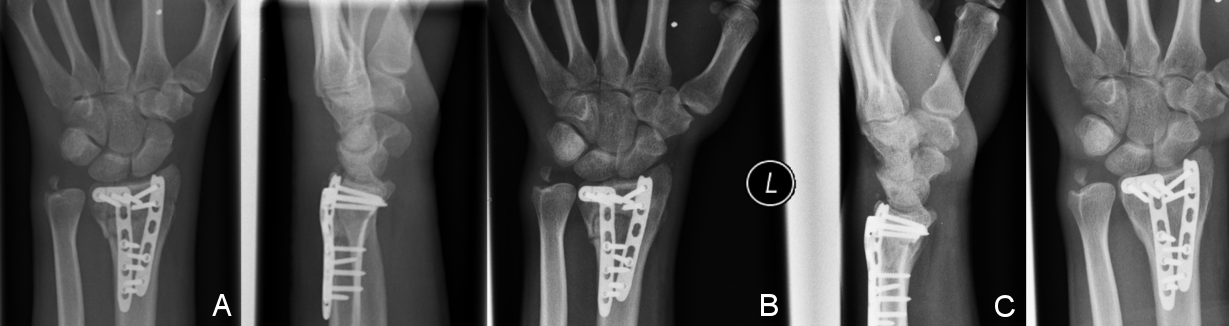

Figure 1: Radiographic follow-up series of a 46-year-old female patient with an AO 23C3 fracture, treated through a dorsal approach with 2.4 mm LCP (Synthes®). A) Postoperative x-ray with excellent reduction. B) Follow-up radiographs after 12 weeks. C) Follow-up radiograph one year after trauma with excellent radiological fracture consolidation and no significant loss of reduction.